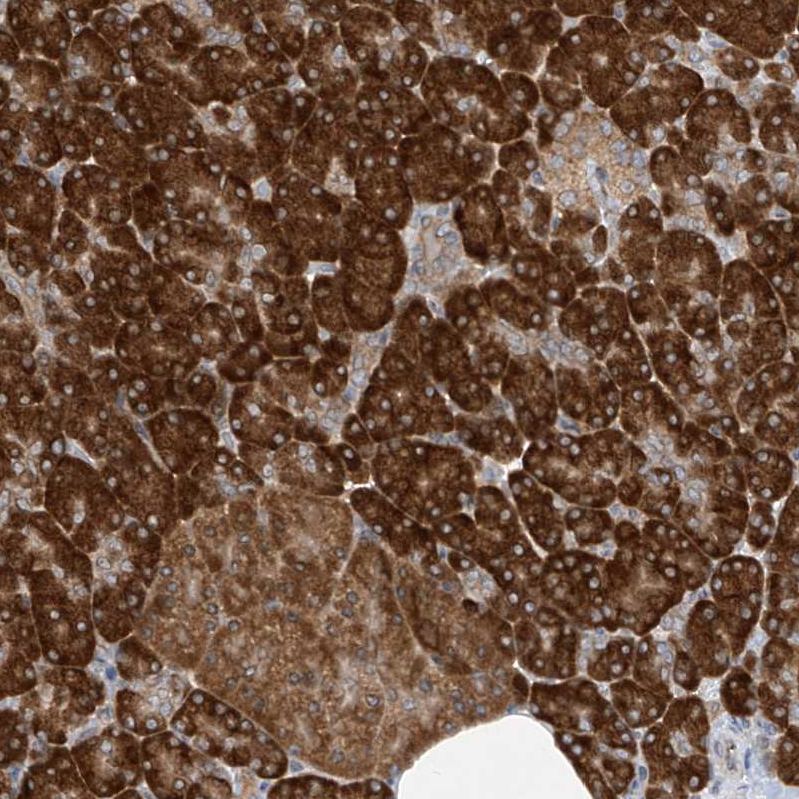

Immunohistochemical staining of human pancreas shows strong cytoplasmic-membranous positivity in exocrine glandular cells moderate cytoplasmic-membranous positivity in endocrine glandular cells.